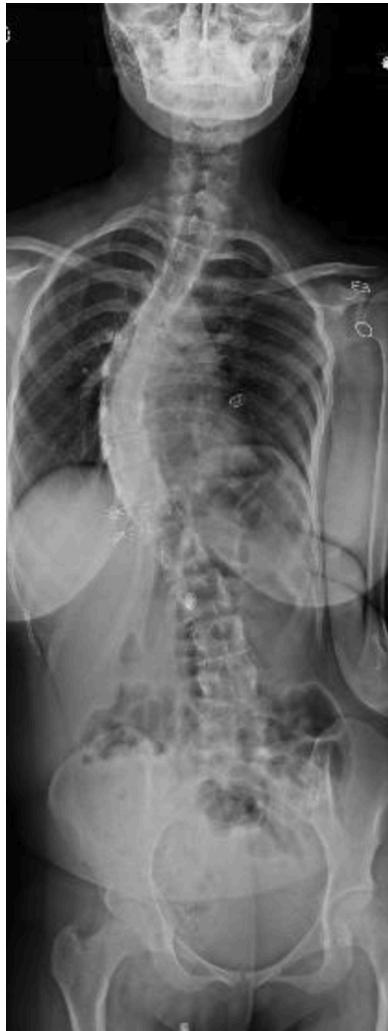

Scoliosis

Deformities

Scoliosis Classification

- Adolescent Idiopathic Scoliosis

- Infantile Idiopathic Scoliosis

- Congenital Scoliosis

- Neuromuscular Scoliosis: Irregular spinal curvature caused by disorders of brain, spinal cord, and muscular system

Adolescent Idiopathic Scoliosis

- Definition: Coronal plane spinal deformity most commonly presenting in adolescent girls from ages 10 to 18

Imaging:

Severity Grades:

- Mild: 10-25°

- Moderate: 25-45°

- Severe: >45°

Treatment Based on Severity:

- Observation: Mild curves, depending on age and skeletal maturity

- Bracing: Moderate curves (25-45°) in growing patients

- Surgery: Severe curves (>45°) or progressive curves